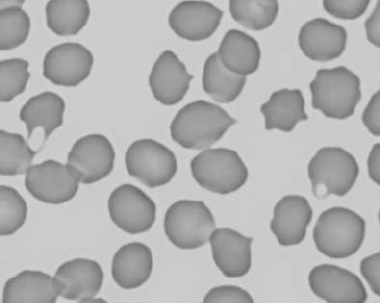

See Figs 1.3–1.24 for pictures of various types of RBC morphology.

Figure 1.22 New methylene-blue-stained Canine blood film showing reticulocytes (also see color section).